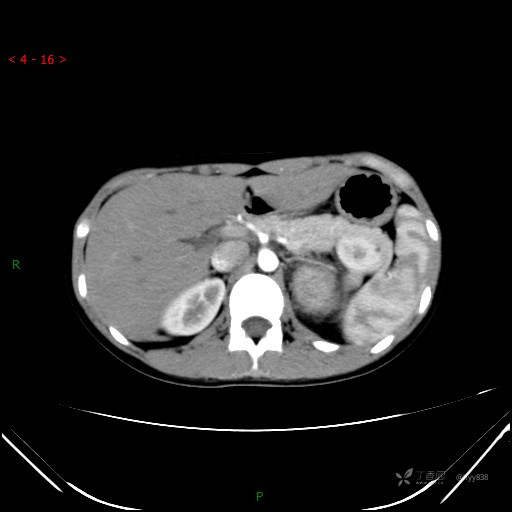

增强静脉期